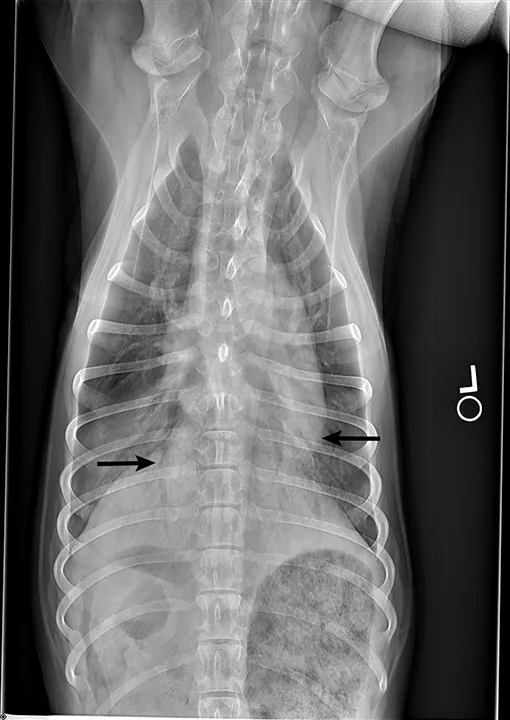

Blood pressure was decreased (85 mm Hg) on Doppler ultrasound. Oxygen saturation was initially 92% but increased to 98% with flow-by oxygen supplementation via mask (4 L/minute). Initial blood work showed mild hyperlactatemia (3.1 mmol/L; reference range, 0-2.5 mmol/L), packed cell volume of 54%, and total solids at 6.8 g/dL. Chest radiography was performed with oxygen supplementation and revealed a moderate to severe caudodorsal interstitial to alveolar lung pattern (Figures 1 and 2).

Radiograph showing air bronchograms consistent with noncardiogenic pulmonary edema (arrows). Atelectasis, which would be evident with shifting of the heart to the left or right, is not present.

Radiographs showing caudodorsal alveolar pattern consistent with noncardiogenic pulmonary edema (arrows). Edema is caudodorsal and bilateral. The heart size is normal, and there is no elevation of the airways that would indicate left-sided heart enlargement. Sternal contact of the heart, which might suggest right-sided heart enlargement, is minimal.

The caudodorsal, bilateral, interstitial to alveolar pattern seen on radiographs is most consistent with noncardiogenic pulmonary edema (NCPE). Other differential diagnoses typically include cardiogenic edema or pneumonia. However, because Charlie was 6 months of age with a normal heart size and no murmurs or arrhythmias auscultated, cardiogenic edema was less likely. Expected pulmonary changes to the lungs are more diffuse with fungal or viral pneumonia or more discrete with bacterial pneumonia. NCPE was most likely in this patient because of the caudodorsal, bilaterally symmetric pattern and history of presumptive electrocution.